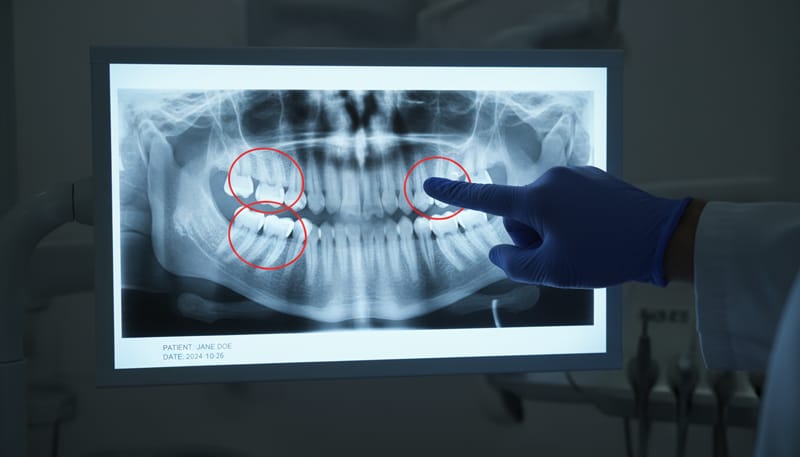

- Đánh giá toàn diện: Nha sĩ sẽ tiến hành thăm khám lâm sàng, chụp X-quang (panoramic, cephalometric), lấy dấu hàm để phân tích kỹ lưỡng cấu trúc xương hàm, tình trạng răng và khớp cắn của bạn.